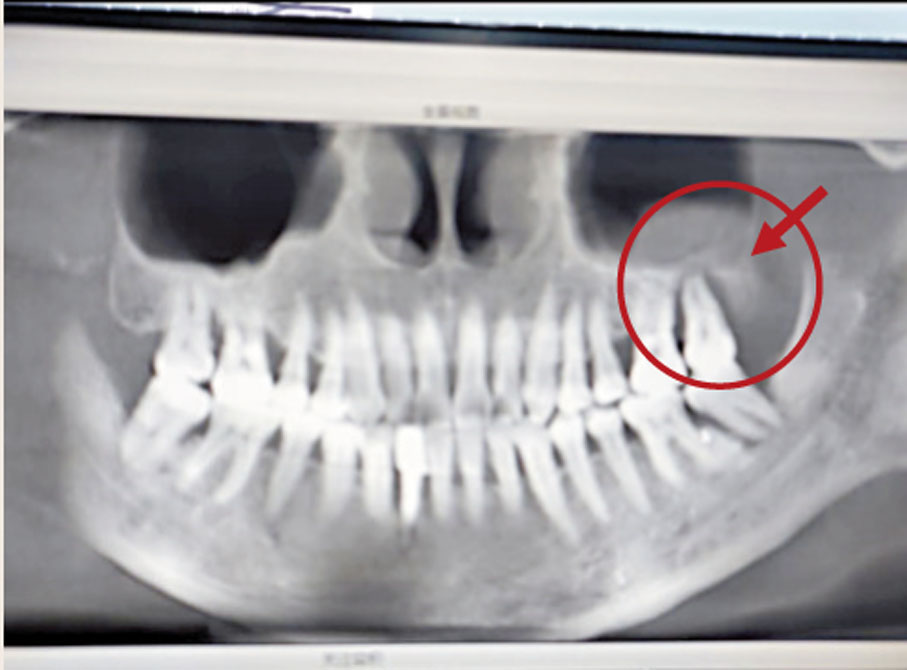

那從三個不同的格式維度去了解的話,部位的定義最大的話語權,當然是家居風水,首先大門代表口,而大門兩側的牆身代表牙藏牙骨;在兩邊的傢俬,可動但又不會隨意搬動,就是牙齒,而周遭的雜物就是牙肉。如果雜物過多,又不協調,壓到電線或電錶就會有牙神經線相關的問題。上圖標誌斜線的空格就是雜物房,由於雜物過多兼蓋住電錶箱,而這位置則在大門左手邊。注意圖左的X光片,圈着的位置正是左面牙肉發炎病變的地方!

至於牙肉的五行基理就是土,戊土(大範圍)或己土(細範圍),所謂「塵歸塵,土歸土」,就是形容我們的身軀,所以土就是肌肉細胞,在右圖的八字內,可見到乙木細菌剋己土,牙肉受細菌侵略,己土不斷重複到時柱,壞牙肉細胞不斷增生,成了病變的牙肉群了。